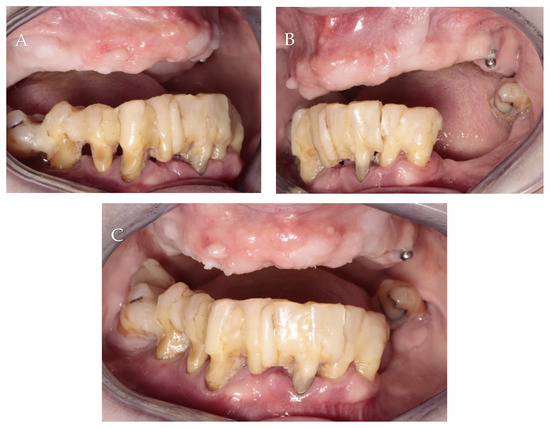

3.1. Patient Information, Diagnosis and Treatment Plan

3.2. Surgery 1—Teeth Extraction and Periodontal Lesion Enucleation with Simultaneous Implantation

3.3. Surgery 2—Apically Positioned Partial-Thickness Flap (APPTF) in Combination with Free Gingival Grafts (FGGs)

3.4. Results